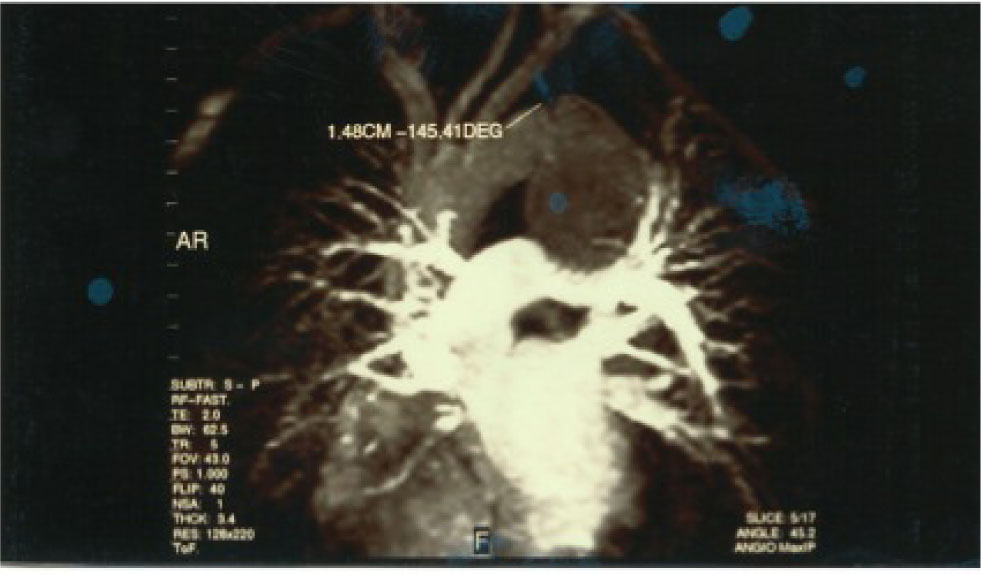

Fiber laryngoscopy showed an immobile left vocal cord in the paramedian position compatible with left recurrent laryngeal nerve paralysis. Further otolaryngological examination showed no abnormality. The laboratory findings were normal. In the potential suspect of an aortic injury, the patient underwent contrast material-enhanced spiral computer tomography (CT) of the chest. Moreover, because of its superior capability in depiction of functional information regarding flow patterns and luminal communications, MR imaging of the chest was also performed. At CT, MR and angioMR imaging a post-traumatic aortic pseudoaneurysm was revealed: concomitant compression of the left broncus was shown as well (Fig. 1, 2). The aortic pseudoaneurysm was consequently repaired by implantation of an endovascular stent graft under local anesthesia. The patient was discharged 10 days later, and at the 3-years follow-up visit the hoarseness and the dysphonia had resolved completely.

Angio MRI: presence of pseudo-aneurysm of the descending thoracic aorta compressing the bronchus of the left and probably the left recurrent nerve. At the level of the origin of the descending thoracic enjoying a break from the intimate closed chest trauma.